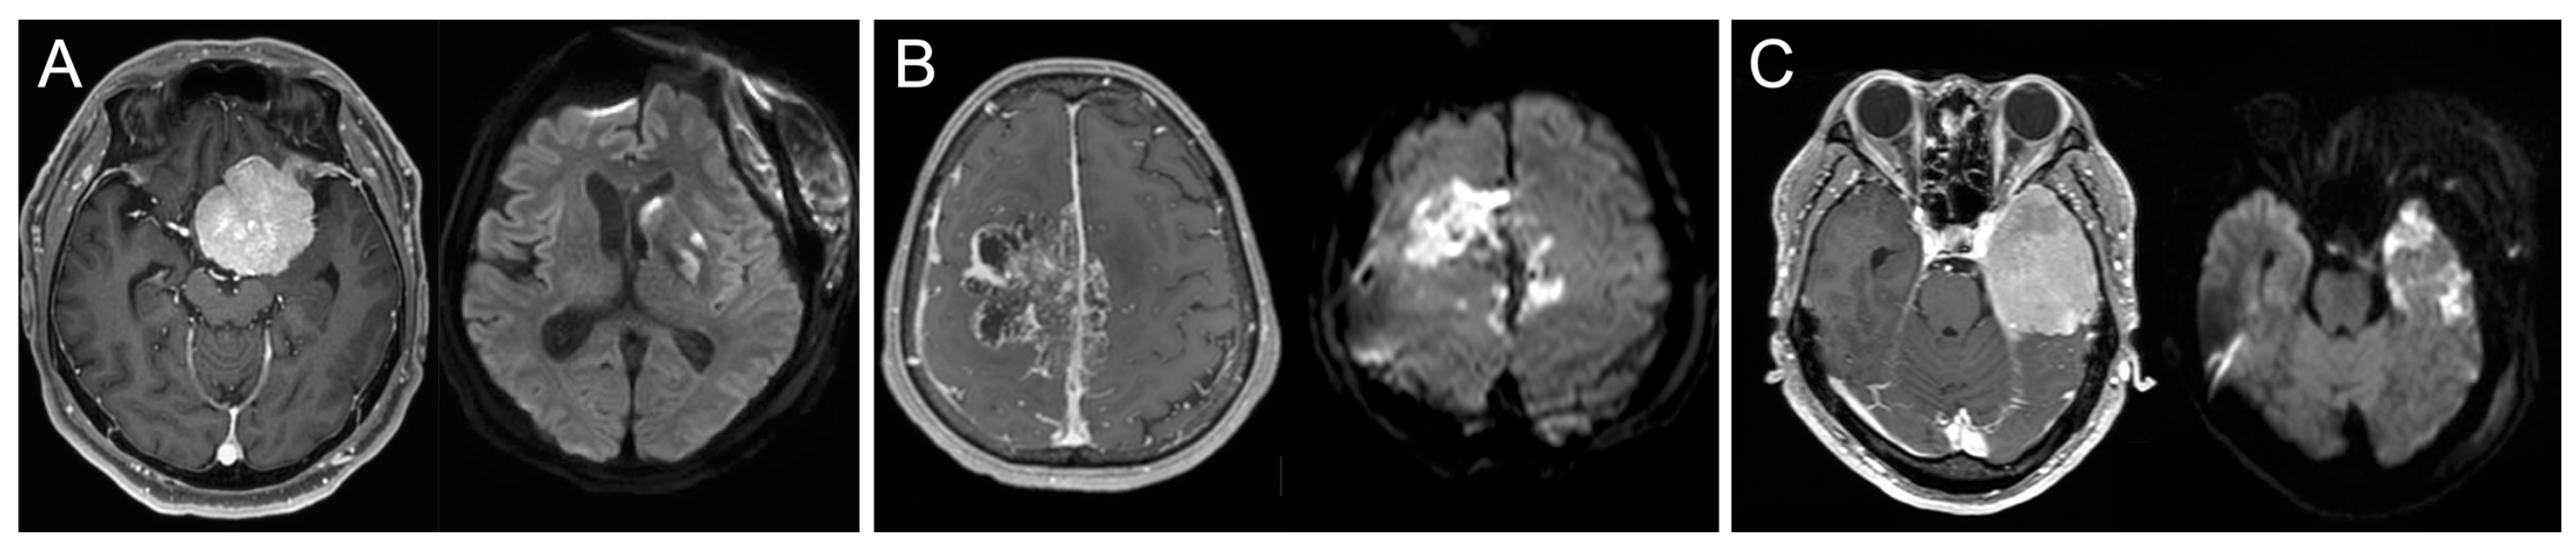

3.2. Early Postoperative MRI Findings and Risk Factors for Postoperative Infarction

4.2. Role of Early Postoperative MRI to Detect Ischemia after Meningioma Resection